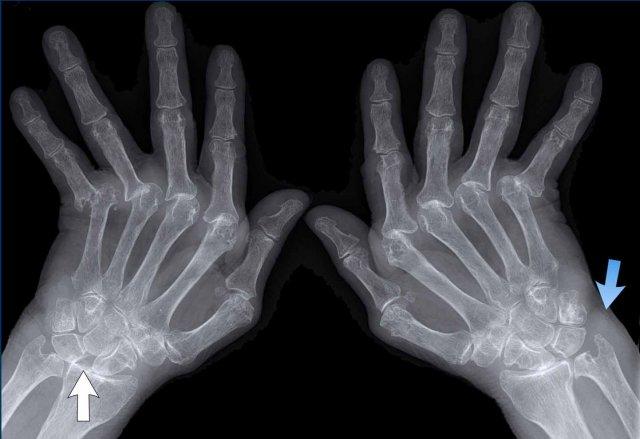

Ngón xúc xích

Hình ảnh điển hình của viêm ngón tay (dactylitis) “ngón xúc xích” với phù nề mô mềm và biến dạng bút chì trong cốc tại khớp liên đốt xa (DIP) 1-2 và 5 của bàn tay trái ở bệnh nhân viêm khớp vảy nến.

Lưu ý rằng các khớp bàn ngón tay (MCP) không bị tổn thương (khác với viêm khớp dạng thấp).